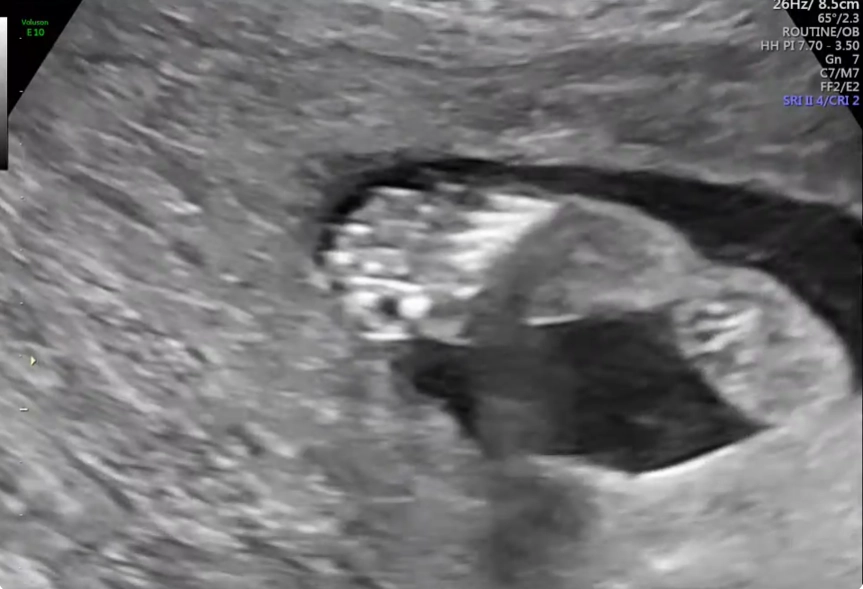

Cứng đa khớp bẩm sinh (Arthrogryposis Multiplex Congenita - AMC)/Chuỗi biến dạng do thai nhi bất động/giảm động (Fetal Akinesia/Hypokinesia Deformation Sequence - FA(H)DS)